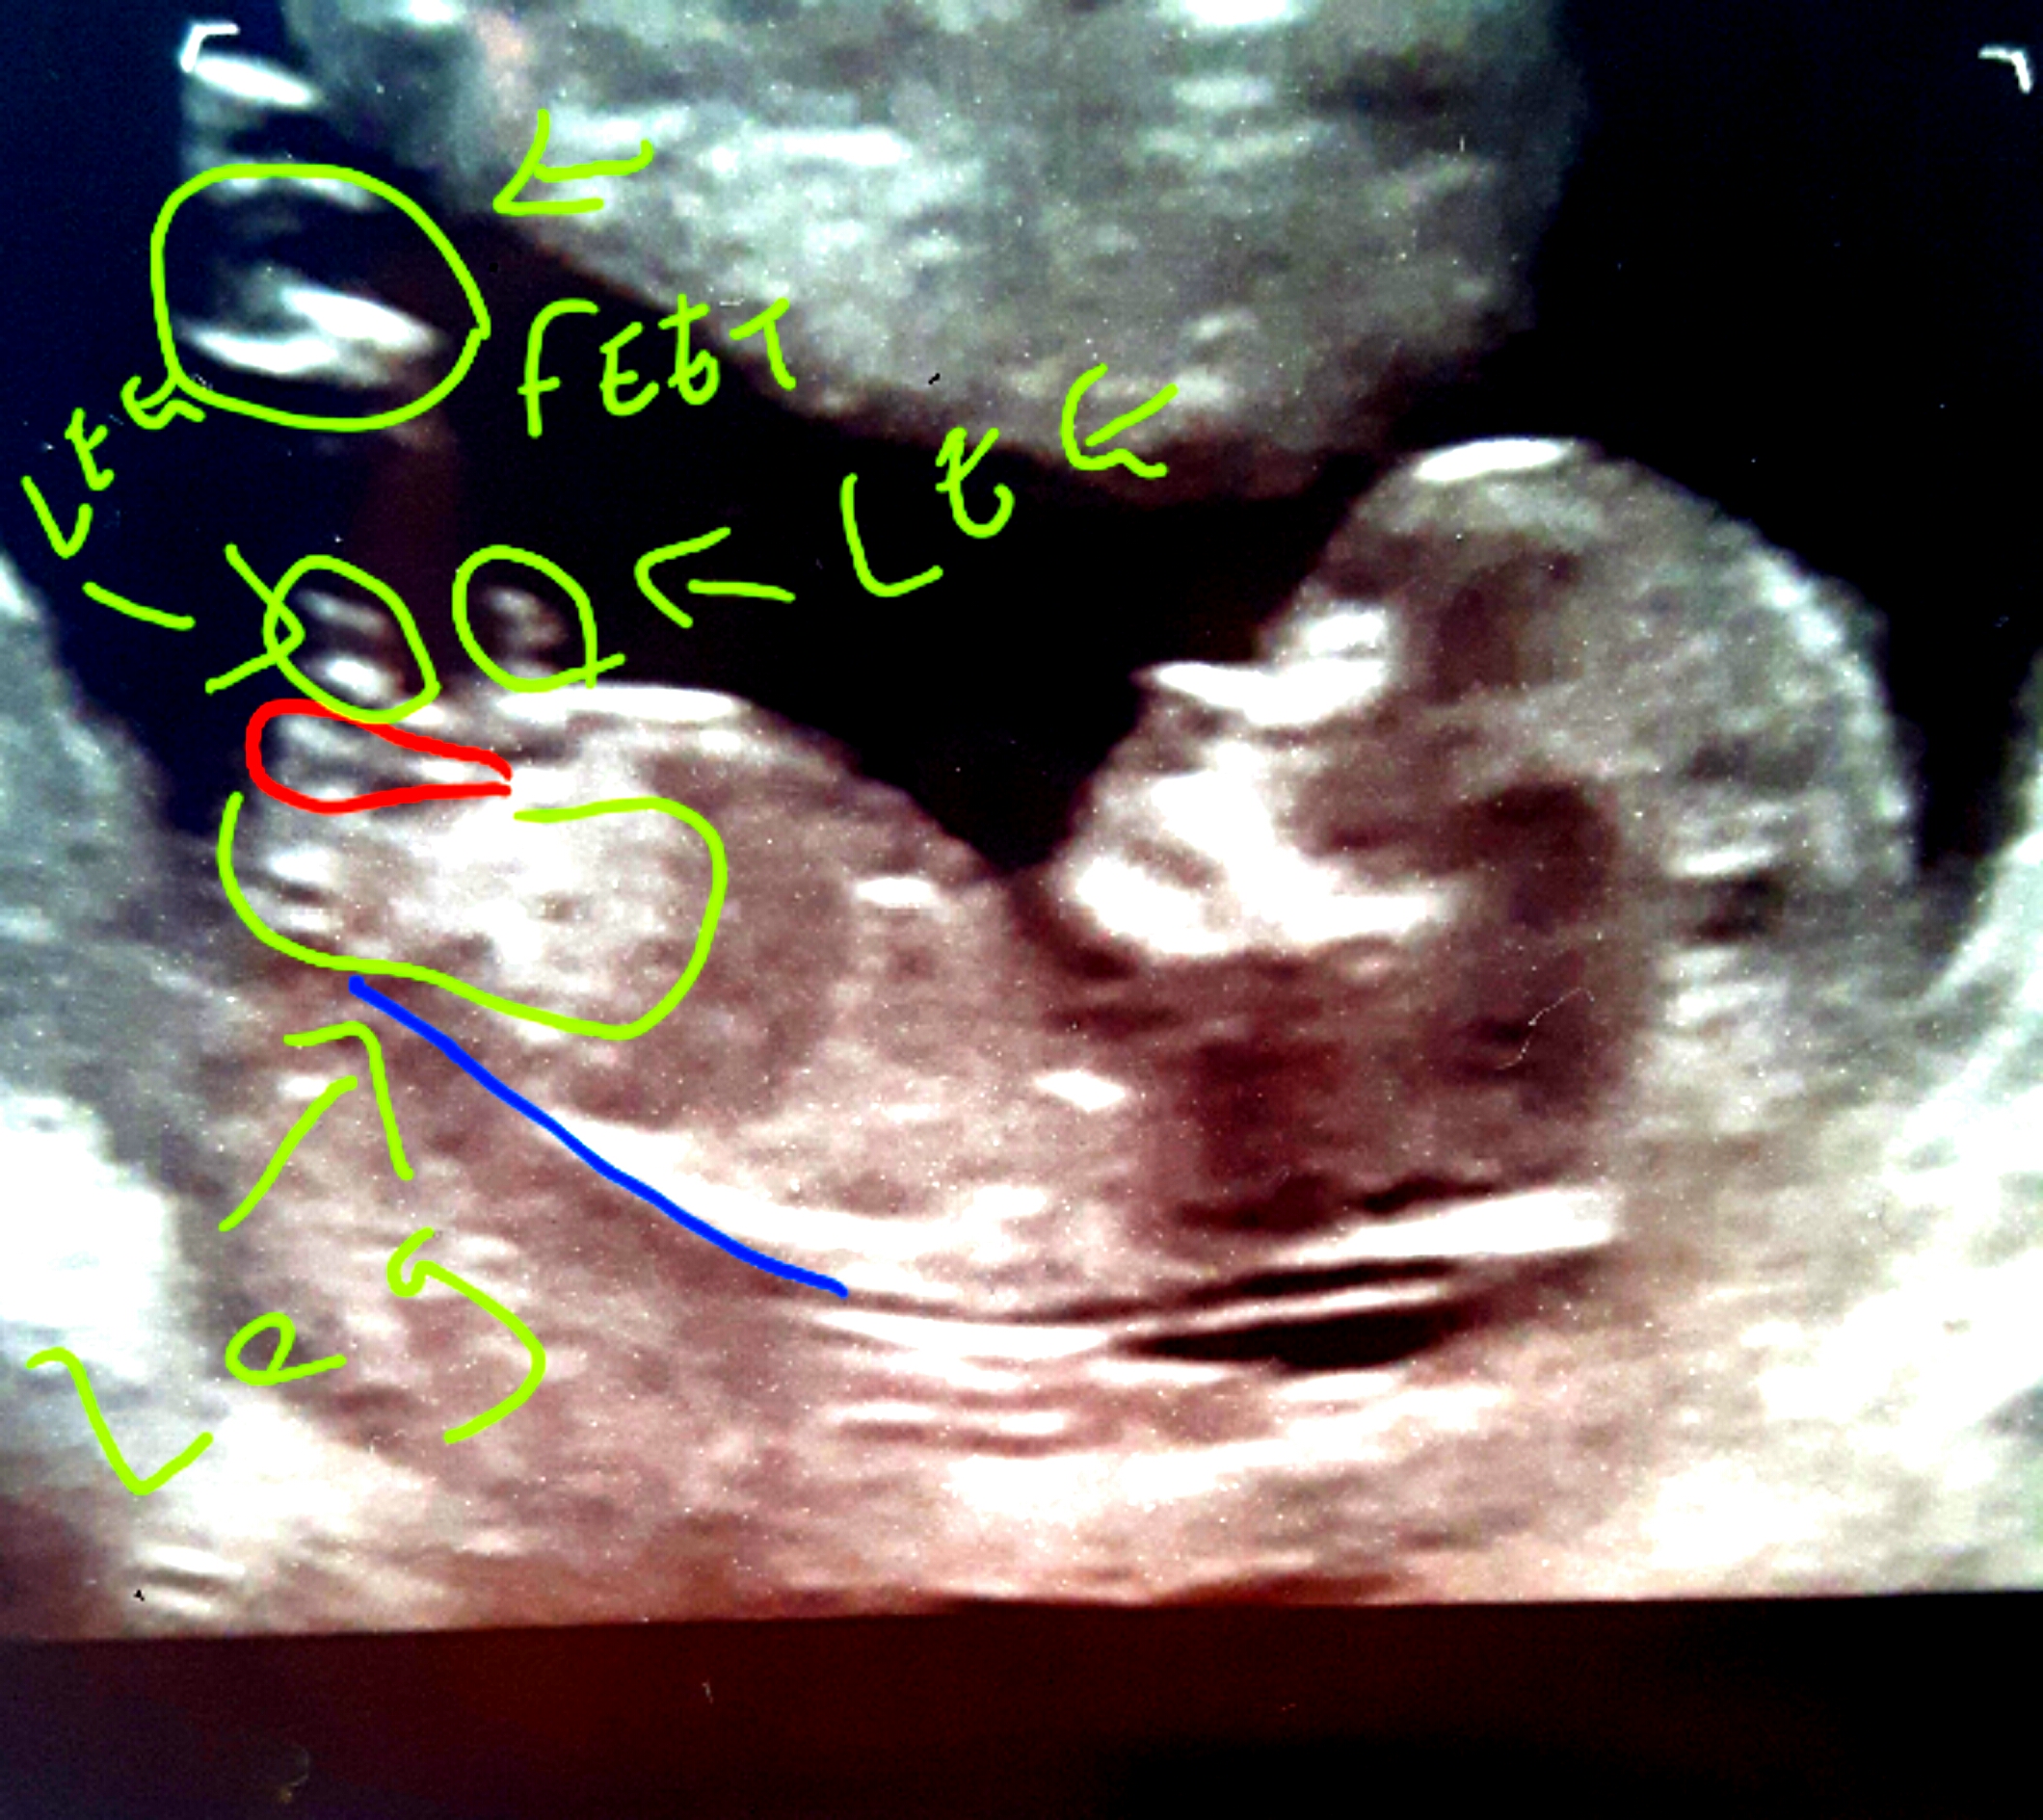

Hi everyone. Any thought? Lots of people on other groups have said boy. Only couple have said girl. My scan picture is a tricky one. But i can see a forked nub and i think its a girl.

This is how im seeing it? Xx